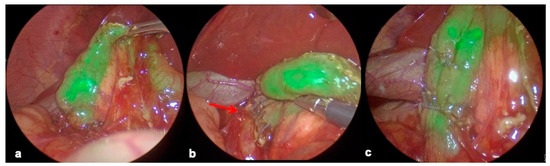

2.4.3. Duodenal Web Localization